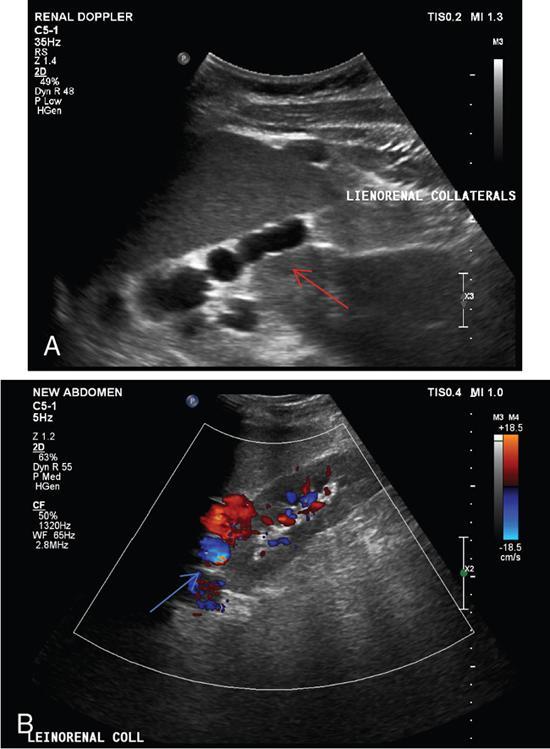

Shrinivas B. Desai, Ritu K. Kashikar, Aman Snehil, Ajay Jhaveri Cirrhosis is a late stage of irreversible scarring of the liver causing abnormality in liver structure and function. Multiple conditions and factors can cause repeated liver damage and scarring ultimately leading to cirrhosis. The most feared complication of liver cirrhosis is the development of hepatocellular carcinoma (HCC). Portal hypertension (PHT) is seen with a variety of conditions but cirrhosis happens to the most important cause. Imaging plays a vital role in noninvasive diagnosis and treatment planning of both cirrhosis and PHT. Liver imaging reporting and data system (LI-RADS) is a standardized reporting system assigning an observation risk of representing HCC. This chapter focuses on discussing aetiologies and imaging of PHT with a lucid review of L1-RADS 2018 version. The portal blood circulation is a unique circulatory circuit as it connects two capillary beds between the liver parenchyma at one end and the gastrointestinal tract and splenic parenchyma at the other end. The portal system ramifies in the liver and ultimately ends in the hepatic sinusoids from where the blood ultimately drains into the inferior vena cava (IVC). The portal vein (PV) originates from the capillary beds in the stomach, intestine and the spleen. The main PV is formed behind the neck of the pancreas by the confluence of the superior mesenteric vein (SMV) and splenic vein. It continues to the porta hepatis where it bifurcates into the left and right branches as it carries nutrient rich but oxygen poor blood to the liver (Fig. 9.9.1). The PV makes up for 75%–80% of the liver’s blood supply while the hepatic artery which arises from the celiac trunk makes up for the remaining 25%. A pathological increase in the portal venous pressure is referred to as PHT. PHT is most often a sequel of chronic parenchymal liver disease and leads to major life-threatening complications due to bleeding from the collateral circulation (most commonly oesophageal varices). Direct measurement of portal pressure (PP) is invasive and often not feasible in most patients and thus imaging plays an important role in the diagnosis of PHT and its complications. The normal portal venous pressure ranges between 5 and 10 mmHg, which is the equivalent of 7–14 cm H2O. The normal hepatic venous pressure gradient (HVPG) is the pressure gradient between the PV and the IVC, is typically 1–5 mmHg. Presence of PHT is indicated by a wedged hepatic venous pressure of more than 5 mmHg. Other definitions include a splenic pressure of more than 15 mmHg or an intraoperative PP of greater than 30 cm H2O. The complications of PHT are seen when HVPG is greater than 10 mmHg and hence this value defines clinically significant PHT. Variceal bleeding is seen with a pressure greater than 12 mmHg. In ideal conditions, the portal circuit is a high flow, low resistance circuit as it has to allow substantial flow rates of 700–1000 mL/min to the hepatic parenchyma from the gastrointestinal tract. Anatomical changes in the organization of the hepatic lobule can result in rise in the portal resistance. These can occur in the form of collagen deposition in the space of Disse, fibrotic scars formed due to regenerative nodule (RN) formation, loss of normal elasticity of the endothelium and distal venous thrombosis. Changes in splanchnic haemodynamics due to factors that increase splanchnic blood flow and increase in intrahepatic vascular resistance due to transformation of stellate cells into myofibroblasts also contribute to the increase in PP gradient. In Western countries, alcoholic cirrhosis and viral cirrhosis are the leading causes of PHT and oesophageal varices. The viral causes form majority of cases leading to cirrhosis and PHT in the Far East and Middle Eastern countries while Schistosomiasis remains an important cause in the African countries. Worldwide, nonalcoholic steatohepatitis (NASH) and hepatitis C are the emerging causes of chronic liver disease (CLD) and PHT. PHT can be classified as cirrhotic and noncirrhotic depending on whether it is associated with cirrhosis or not. This distinction is important as noncirrhotic causes like PV thrombosis are at high risk of development of bleeding but tend to have a better chance of surviving a variceal bleed than a patient with decompensated alcoholic cirrhosis due to preserved hepatic synthetic functions in the former. PHT can also be classified on the basis of the location of the pathology into prehepatic, hepatic and posthepatic causes. Hepatic causes can further be divided into presinusoidal, sinusoidal and postsinusoidal. The causes of portal hypertension have been denoted in Table 9.9.1. The direct measurement of the PP by measuring the HVPG is invasive, expensive not readily available in all patients. Thus, imaging plays an important role in the diagnosis of PHT. Various modalities are used for the imaging diagnosis of PHT. Ultrasonography (USG) and Doppler evaluation have the advantage of being inexpensive, readily available and bedside modality (Table 9.9.2). The role of ultrasound and Doppler in imaging of PHT is to: Grey scale imaging is useful in evaluating the splenoportal anatomy. The evaluation should begin with the liver morphology. Signs of cirrhosis like nodularity of the liver surface with relative atrophy of the right lobe and prominence of the left lobe and caudate should be looked for. Hepatic echotexture appears coarse and more echogenic (Table 9.9.3). Increase in portal venous diameter is a sign of PHT (Fig. 9.9.2). Portal venous diameter of more than 13 or 15 mm has low sensitivity for diagnosing PHT of only 40%–12.5%, respectively. Absolute measurement of the portal diameter as a sign of PHT is also fallacious as in presence of collateral circulation or hepatofugal flow; there may actually be a decrease in the PV diameter. Therefore, a more accurate sign is respiratory variation of PV diameter. An increase in PV diameter of less than 20% with deep inspiration has been reported to indicate PHT with a sensitivity of 80% and specificity of 100%. This has been reported to be an accurate indicator of cirrhosis. Hepatic vein straightness, uniformity of vein wall echogenicity and visualization of at least 1 cm segment of the hepatic vein are the parameters used for evaluation. Splenomegaly is defined as bipolar splenic diameter of greater than 12 cm or largest splenic cross-sectional area passing through the hilum of greater than 45 cm2, and occurs secondary to PHT (Fig. 9.9.3). A total of 65%–80% patients with cirrhosis have splenomegaly on ultrasound. Patients with cirrhosis due to viral hepatitis and primary biliary cirrhosis show splenomegaly more frequently than those with alcoholic cirrhosis. This is an accurate sign of PHT. USG is extremely sensitive with respect to detecting subclinical ascites. Perihepatic space is the most usual site of visualization of minimal ascites. In normal subjects, this ratio is approximately 0.07 and a value above 0.1 suggests the diagnosis of PHT with a 95% sensitivity and specificity. The normal spectral waveform of the hepatic artery is a low resistance flow pattern with forward flow in diastole and a resistivity index in the range of 0.5–0.7. In PHT, the resistivity index of the hepatic artery increases with high resistance flow pattern due to increased peripheral vascular resistance. Resistance index (RI) > 0.78 in the intrahepatic branches of the hepatic artery has been reported to have a sensitivity of 50% and a specificity of 100% for the detection of PHT (Fig. 9.9.11). Pulsatility index (PI) > 1.05 suggests severe PHT with a sensitivity of 86% and specificity of 88% (Fig. 9.9.11). Patency of hepatic veins should be evaluated to rule out Budd–Chiari syndrome as a cause of PHT. The normal hepatic venous waveform (HVW) reflects right atrial activity and this results in a triphasic waveform with one positive and two negative waves. In PHT, this waveform becomes monophasic or biphasic. A monophasic HVW has a sensitivity and specificity of 74% and 95%, respectively, in the diagnosis of severe PHT (Fig. 9.9.12). Dilatation of the splanchnic veins – the SMV and the splenic vein – more than 11 mm are suggestive of PHT with a sensitivity and specificity of 72% and 100%, respectively. A reduction in the respiratory variation of the splenic vein and SMV to less than 40% had a sensitivity and specificity of 79.7% and 100%, respectively, for the diagnosis of PHT (Fig. 9.9.13). The splenic artery reveals an increase in the resistivity index and an RI of >0.63 and a PI of >1 have a sensitivity and specificity of 84.6% and 70.4% for the diagnosis of PHT. Presence of portosystemic collaterals like patent paraumbilical vein, dilated left gastric and short gastric veins are 100% specific sign for PHT (Figs. 9.9.14–9.9.16). Recanalization of the paraumbilical vein, known as the Cruveilhier–Baumgarten syndrome is observed in 43% of patients with PHT, and this is the easiest collateral to assess during the US examination. Various portosystemic collaterals that occur in PHT have been discussed in details in subsection on CT findings in PHT. No Doppler parameter is considered reliable enough to measure PP with sufficient accuracy for use in clinical practice. Oesophageal varices are often present in patients with portosystemic collaterals. Appearance or increase in number of collaterals along with splenomegaly has a high association with variceal formation and growth. USG helps in diagnosis of prehepatic causes like portal stenosis or thrombosis by demonstrating the patency and morphology of the splenoportal system. Arteriovenous fistulae and tumours causing vascular thrombosis as aetiology can be readily detected. USG helps in diagnosis of features of cirrhosis and thus helps differentiate noncirrhotic causes of PHT. USG allows diagnosis of fatty liver disease, which is an emerging cause of cirrhosis. Among the posthepatic causes, USG aids in establishing the diagnosis of Budd–Chiari syndrome by demonstrating the patency and morphology of the IVC and hepatic veins. Owing to the inability of CT to detect flow direction, portal flow rates or pressure gradients, CT is not the primary modality in diagnosis of PHT. Similar to USG dilatation of portosystemic system is a feature of PHT (Fig. 9.9.17). Changes in cirrhosis if present can be seen in the form of surface nodularity, nodules and fibrous septae. CT plays an important role in diagnosis of portal venous thrombosis and evaluating its extent. An acute thrombus is seen as a hypodense filling defect in the vessel causing distension of the venous lumen. Surrounding fat stranding can be seen. A chronic thrombus appears as an eccentric filling defect usually along the wall and is often associated with decrease in vessel diameter. Calcification may be seen in chronic thrombi. Multidetector computed tomography (MDCT) is a useful tool to evaluate portosystemic collateral circulation and recognize complications of PHT. 3D angiography can help understand portal venous and complex variceal anatomy and plan treatment. The various portosystemic collaterals are discussed below. They can be classified into those draining into superior vena cava (SVC) and those draining into the IVC. Magnetic resonance imaging (MRI) is a noninvasive modality used in the evaluation of PHT without the use of ionising radiation. It provides evaluation of parenchymal abnormalities, collaterals and characterization of tumours (Fig. 9.9.28). Spin echo sequences allow characterization of liver masses and liver parenchyma. Loss of flow void allows for detection of thrombosis. Time-of-flight (TOF) angiography is useful in assessing the portal venous system and allows for successful detection of PV thrombosis. The disadvantages of TOF are motion artefacts caused by breathing, long acquisition times and incomplete coverage of the portal venous system. Novel imaging techniques include phase contrast, T1 mapping and magnetic resonance elastography (MRE). The advantage of phase contrast over TOF imaging is that phase contrast imaging acquires information regarding the flow direction in addition to the information regarding the flow velocity. On-phase contrast images signal within vessel is hyperintense when flow is cranial and hypointense when flow is caudal. Look-Locker imaging technique using gradient echo (GRE) MRI sequences with inversion recovery pulse is used to quantify fibrosis by measuring precontrast T1 relaxation times. Interventions in PHT can be aimed at diagnosis or more commonly at management of complications of PHT. HVPG measurement, which is the gold standard for the diagnosis of PHT, can be achieved through cannulation of the PV. Transjugular hepatic biopsy is another diagnostic invasive technique that also allows indirect measurement of PP. Disadvantages include deterioration of hepatic function caused by diversion of portal venous blood flow and shunt dysfunction. TIPSS is contraindicated in patients with congestive heart failure, severe pulmonary hypertension, severe tricuspid regurgitation and hepatic failure. In this technique, a catheter is advanced from the femoral vein into the outlet of the gastrorenal, usually in the region of the left renal vein. The shunt is then occluded with a balloon and sclerosant is injected retrograde to occlude the gastric varices. Histological development of RNs surrounded by fibrous septae in response to chronic liver injury, progressing PHT and end-stage liver disease is termed as cirrhosis. Although initially considered an end-stage phenomenon in CLD, recent evidence suggests that the histological fibrosis can be reversible in early stages with the initiation of specific therapies, for example, in viral cirrhosis with the initiation of antiviral therapy. The one-year mortality rate in cirrhosis varies widely from 1% to 57% depending on the occurrence of complications. Cirrhosis can have a wide variety of causes ranging from congenital to acquired and infectious to noninfectious. It is also a major aetiologic risk factor for the development of HCC. Imaging plays an important role in aetiologic diagnosis of this diverse entity as well as in the diagnosis and management of its complication and surveillance for oncological transformation.